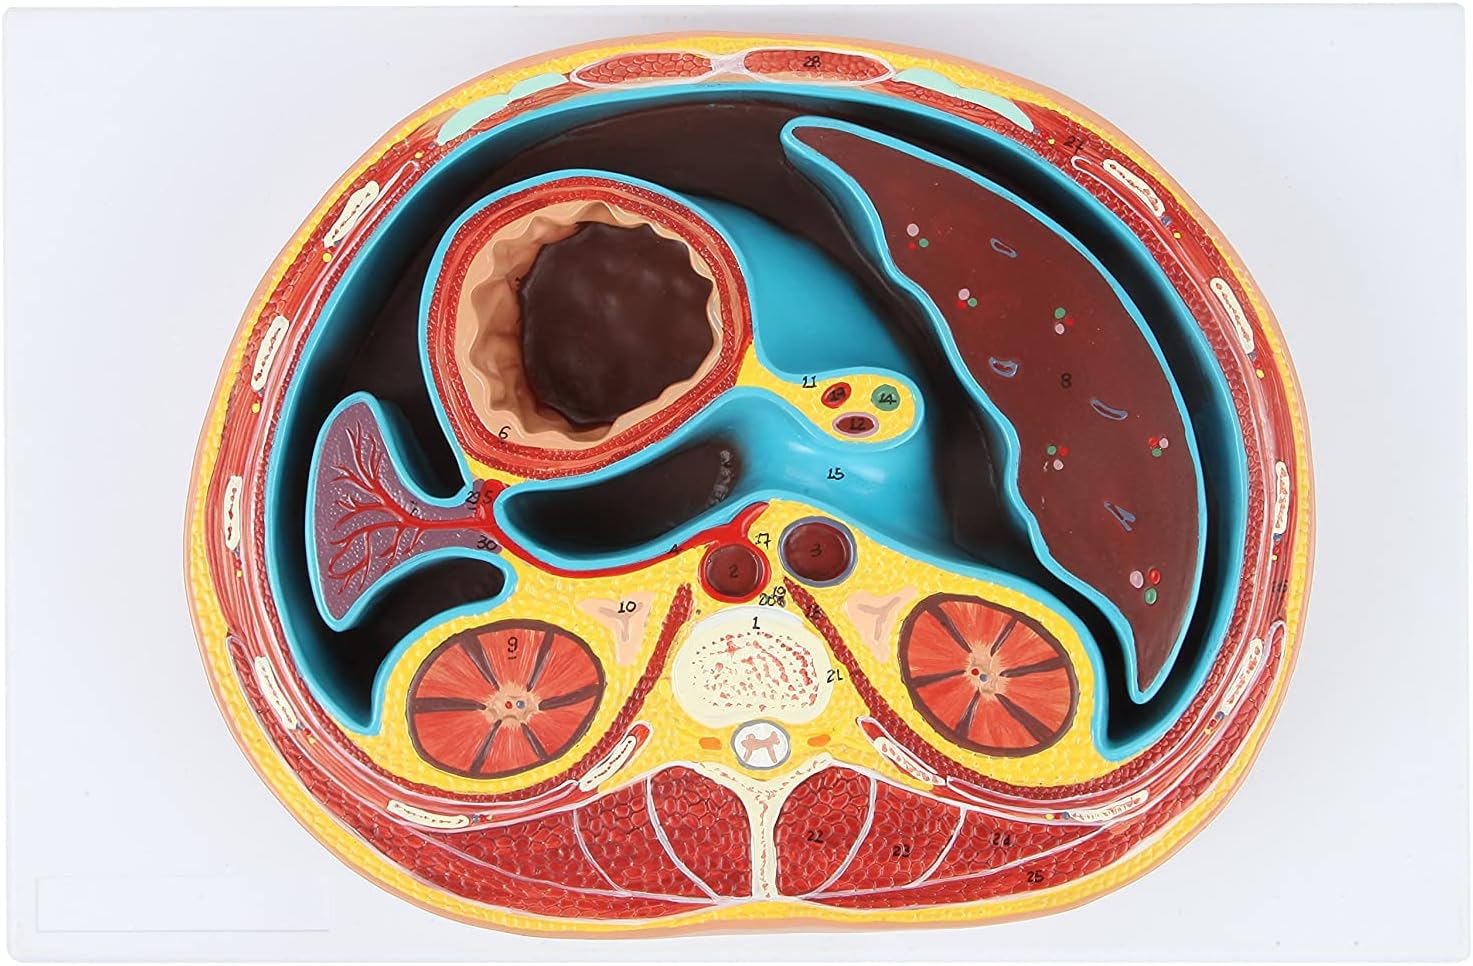

medical device

medical device